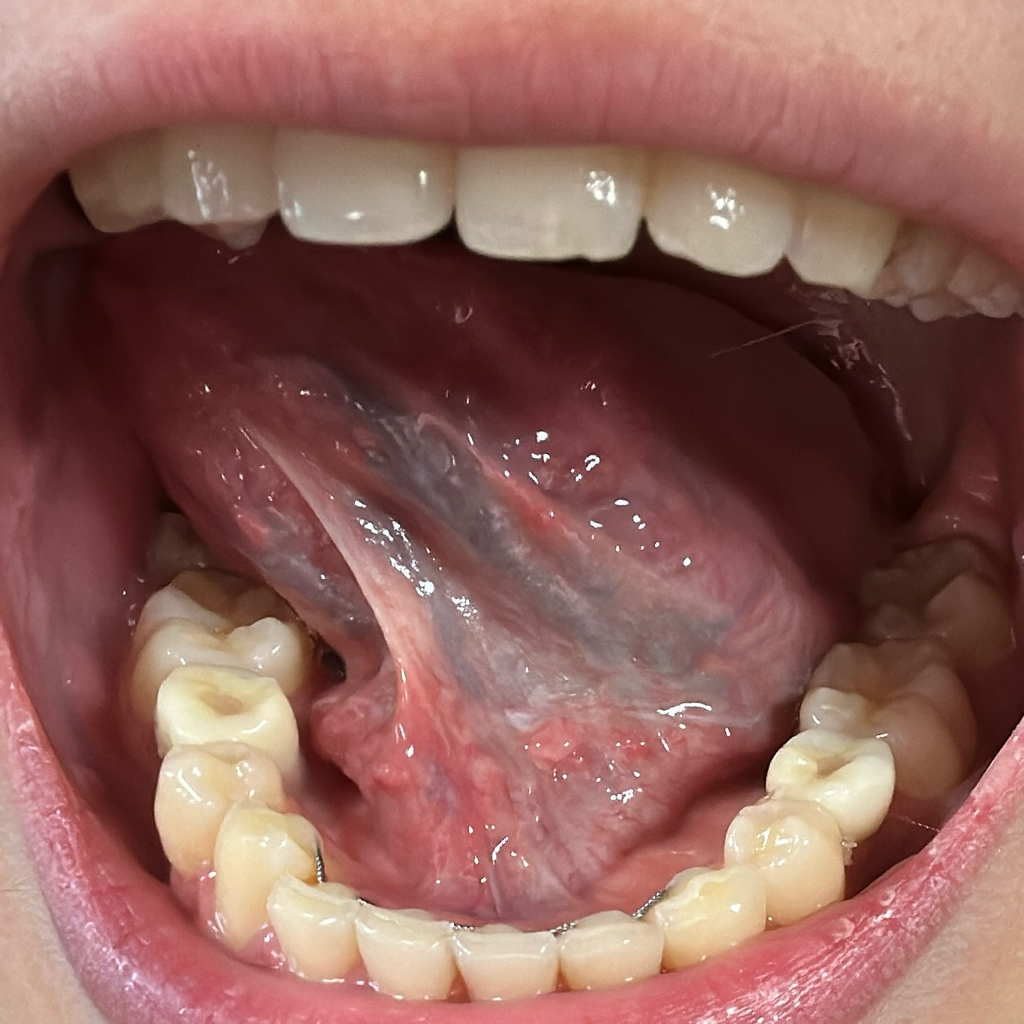

안녕하세요. 이송재 의사입니다. 올려주신 사진을 보았을 때 혀 아래쪽에는 특별한 병변은 관찰 되지 않습니다. 통증이나 다른 증상 없으면 지켜보셔도 됩니다